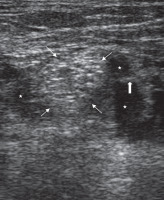

All patients underwent SNB prior to the angiography procedure. Each block was performed by an interventional radiologist (MG) who was experienced in US-guided peripheral nerve block. A posterior popliteal approach to SNB was employed in this study. The patients were placed in the prone position. After skin disinfection, an ultrasound system with a high-frequency linear transducer (9-13 MHz) was positioned to localise the sciatic nerve on the popliteal fossa. After identifying the sciatic nerve as a round, hyperechoic structure (Figure 1), the overlying skin was infiltrated with local prilocaine. A 21-gauge needle was inserted at a 45° to 60° angle to the skin and advanced slowly toward the target nerve in a plane from lateral to medial or medial to lateral direction (Figures 2 and 3). To avoid an incomplete nerve block, the needle insertion point was chosen just above the division of the sciatic nerve. After confirming that the tip of the needle was adjacent to the sciatic nerve, the block was conducted with multiple injections of local anaesthetic to create a circumferential spread around the sciatic nerve (Figure 2 and 3). In all patients, SNB was performed with a standardised mixture of 10 ml of bupivacaine 0.5%, 10 ml of lidocaine 2%, and 10 ml normal saline. The success of the block was defined as a significant relief of pain prior to endovascular treatment. If the patients were not satisfied with pain relief within five minutes, the block was repeated with the same dose of local anaesthetics. Narcotic medications were administered if required. The dose and time of administration were recorded.

Figure 1

Ultrasound image of the pre-injection sciatic nerve in the popliteal fossa. Thin arrows: sciatic nerve; Thick arrow: popliteal artery